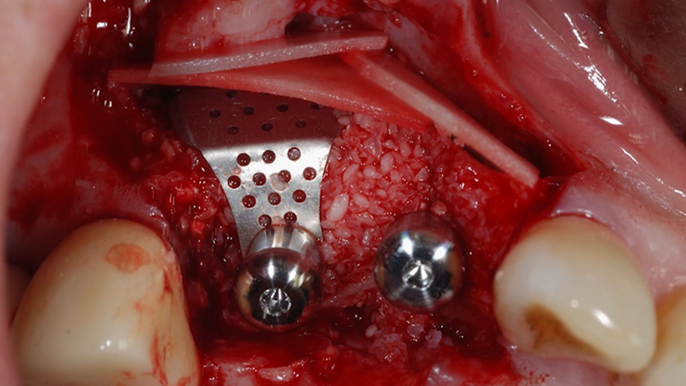

Clinical case: R2GATE GUIDE surgery with GBR

- Courtesy of Dr. Kwang Bum Park, Korea -

Keywords

Dr. Kwang Bum Park, digital guided surgery, bone regeneration, maxillary posterior, #13, #14, guided surgery, GBR, AnyRidge, i-GEN, Mega-Oss, R2GATE, R2GATE Full surgical kit